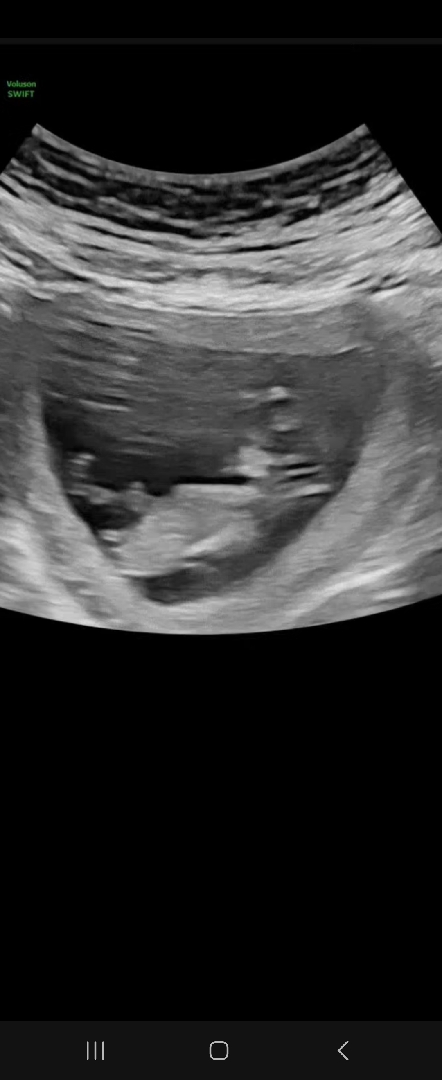

각도법 한번봐주세용!!

11주라서 아직 이르긴하지만 한번부탁드립니다!!!